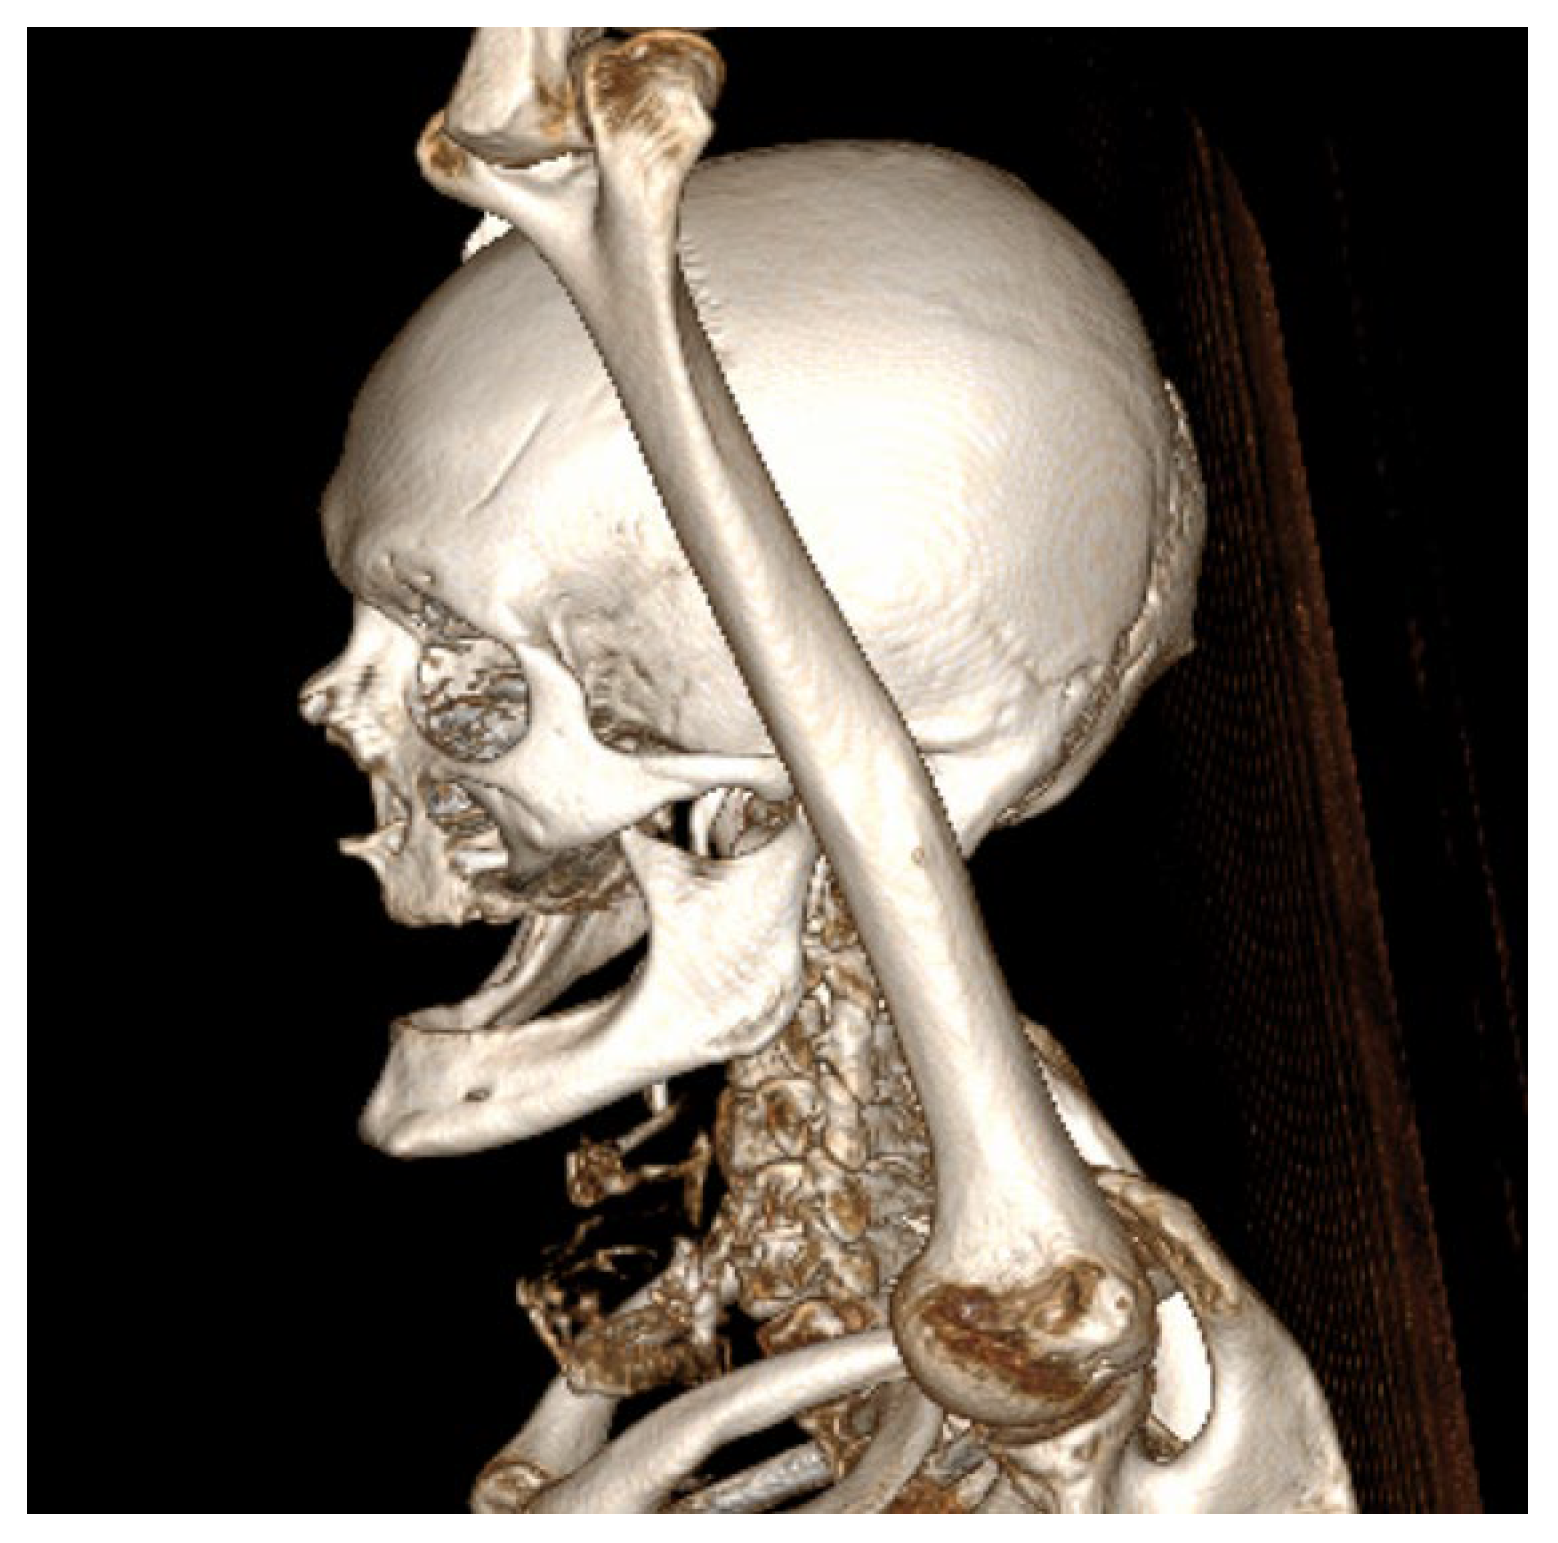

Figure 4.

Three-dimensional CT reconstruction in left lateral view demonstrating the craniofacial skeleton, cervical vertebrae, and upper thoracic cage with no bone destruction.

It remained confined to the left side, without crossing the midline. The radiologic appearance was suggestive of a necrotic neoplasm or, less likely, an infectious etiology. Additional findings included a few punctate calcifications within the left parotid gland and an associated 4 mm hypodense area. A well-circumscribed, cystic-appearing lesion measuring 15 mm was also noted in the left subclavicular region, radiologically consistent with a possible lymphangioma. The carotid-jugular vascular axis was patent bilaterally with preserved caliber, although parietal calcifications were observed at the carotid bifurcations on both sides.